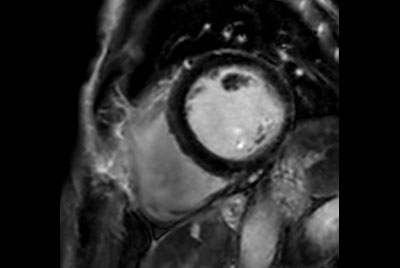

Myocardial infarction with T1/T2 Mapping

Cardiac infarction with Compressed SENSE

Cardiac infarction with fat-free mDIXON imaging

Acute myocardial infarction

30 minute Cardiac Function and Fibrosis at 1.5T

30 minute Cardiac Function and Fibrosis at 3.0T

Cardiac MRI - Arrhythmia patient